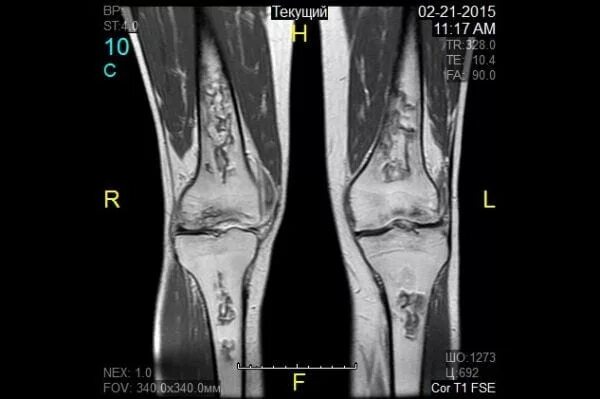

Кт суставов что показывает